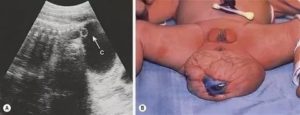

Дополнительные обследования, позволяющие достоверно определить перекрут яичка, включают диафаноскопию, УЗИ органов мошонки и УЗДГ сосудов мошонки.

Эхографическим признаком, указывающим на жизнеспособность яичка, является неизмененная эхоплотность органа; тестикулы с пониженной или неоднородной эхогенностью, как правило, нежизнеспособны.

В диагностировании участвует и аппарат УЗИ, который помогает обнаруживать отсутствие кровотока в пострадавшем органе.

| Сонография | При данном исследовании перекрут яичка выглядит как неоднородное (негомогенное) изображение с участками сниженной и повышенной эхогенности. Также наблюдается утолщение тканей мошонки, отек придатка и незначительное гидроцеле |

| Доплеровское УЗИ | Метод позволяет увидеть обеднение или полное прекращение кровотока в яичке, которое наблюдается при патологии |